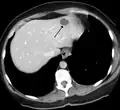

Capillary hemangioma

Strawberry naevus, H&E stain

The majority of IHs can be diagnosed by history and physical examination.[32] In rare cases, imaging (ultrasound with Doppler, magnetic resonance imaging), and/or cytology or histopathology are needed to confirm the diagnosis.[33][34] IHs are usually absent at birth or a small area of pallor, telangiectasias, or duskiness may be seen. A fully formed mass at birth usually indicates a different diagnosis. Superficial hemangiomas in the upper dermis have a bright-red strawberry color, whereas those in the deep dermis and subcutis, deep hemangiomas, may appear blue and be firm or rubbery on palpation. Mixed hemangiomas can have both features.[32] A minimally proliferative IH is an uncommon type that presents with fine macular telangiectasias with an occasional bright-red, papular, proliferative component. Minimally proliferative IHs are more common in the lower body.[35]

A precise history of the growth characteristics of the IH can be very helpful in making the diagnosis. In the first 4 to 8 weeks of life, IHs grow rapidly with primarily volumetric rather than radial growth. This is usually followed by a period of slower growth that can last 6–9 months, with 80% of the growth completed by 3 months. Finally, IHs involute over a period of years.[36] The exceptions to these growth characteristics include minimally proliferative His, which do not substantially proliferate[35] and large, deep IHs in which noticeable growth starts later and lasts longer.[36] If the diagnosis is not clear based on physical examination and growth history (most often in deep hemangiomas with little cutaneous involvement), then either imaging or histopathology can help confirm the diagnosis.[33][37] On Doppler ultrasound, an IH in the proliferative phase appears as a high-flow, soft-tissue mass usually without direct arteriovenous shunting. On MRI, IHs show a well-circumscribed lesion with intermediate and increased signal intensity on T1- and T2-weighted sequences, respectively, and strong enhancement after gadolinium injections, with fast-flow vessels.[33] Tissue for diagnosis can be obtained via fine-needle aspiration, skin biopsy, or excisional biopsy.[38] Under the microscope, IHs are unencapsulated aggregates of closely packed, thin-walled capillaries, usually with endothelial lining. Blood-filled vessels are separated by scant connective tissue. Their lumina may be thrombosed and organized. Hemosiderin pigment deposition due to vessel rupture may be observed.[39] The GLUT-1 histochemical marker can be helpful in distinguishing IHs from other items on the differential diagnosis, such as vascular malformations.[34]

Liver

Infantile hemangiomas in the liver are found in 16% of all liver hemangiomas. Its sizes are usually less than 1 to 2 cm in diameter. It may show a "flash-filling" phenomenon in which there is a fast enhancement of the contrast material in the lesion instead of slow, centripetal, nodular filling of the lesions in usual hemangiomas. On CT and MRI, it shows rapid filling during arterial phase, with contrast retention in venous and delayed phases.[40]